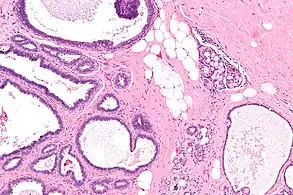

| Micrograph of collagenous spherulosis with the characteristic histomorphology - intratubular eosinophilic material with a spoke-like arrangement. H&E stain. | |

Collagenous spherulosis is characterized by a tubular/cribriform architecture with intratubular eosinophilic material that classically is arranged like the spokes of a wheel ("radial spikes"). There is usually no mitotic activity, and two cells populations (epithelial & myoepithelial) are present, like in benign breast glands.

The lesions are typically small (less than 50 spherules per lesion, less than 100 micrometers in size) and may be multifocal.